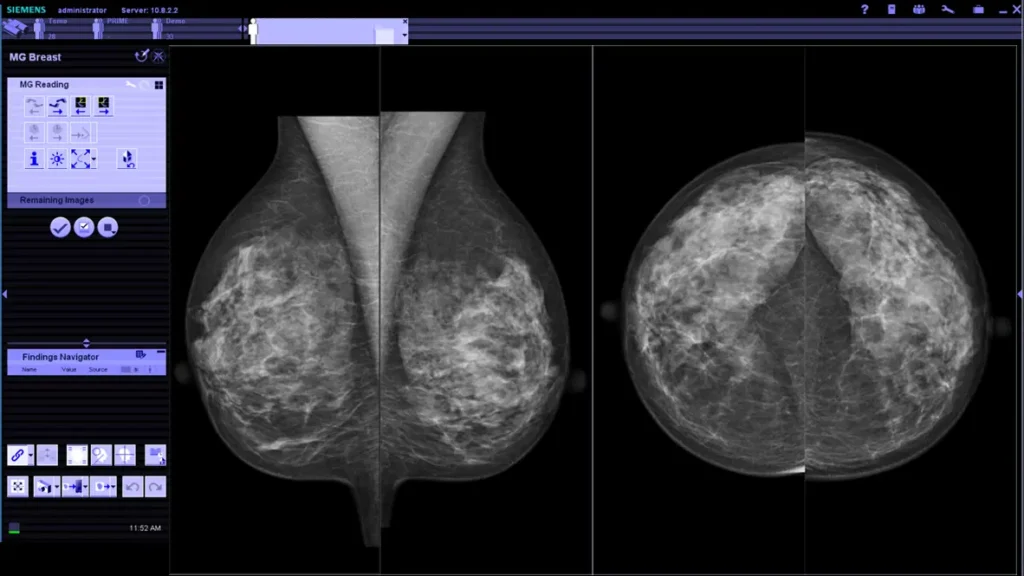

RM 1.5T con BioMatrix

Consistencia de protocolo y calidad de señal para evaluaciones multiparamétricas, favoreciendo precisión en caracterización y seguimiento.